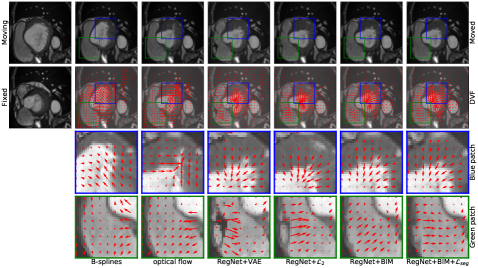

Visual assessment of our proposed methods compared to other approaches on the ACDC dataset is shown in Fig. 2. From the figure, we can see that B-splines [13] and optical flow [11] generate artifacts in the myocardium, especially in the highlighted blue patch shown in the third row. The RegNet+VAE [12] creates unrealistic motion in the right ventricle region, especially in the highlighted green patch shown in the last row, which might be due to penalization of the VAE regularizer mainly focusing on the myocardium only. Our proposed methods, in the last two columns, show improved motion compared to the RegNet+2subscript2\mathcal{L}_{2} with smoother and more biomechanically plausible motion that preserves the geometric features of cardiac structures. The visual results of our proposed methods compared with others on the LV quantification dataset is included in the supplementary material (Fig. 4).

Refer to caption

Figure 2: Visual assessment of registration performance on the ACDC 2017 dataset [5].